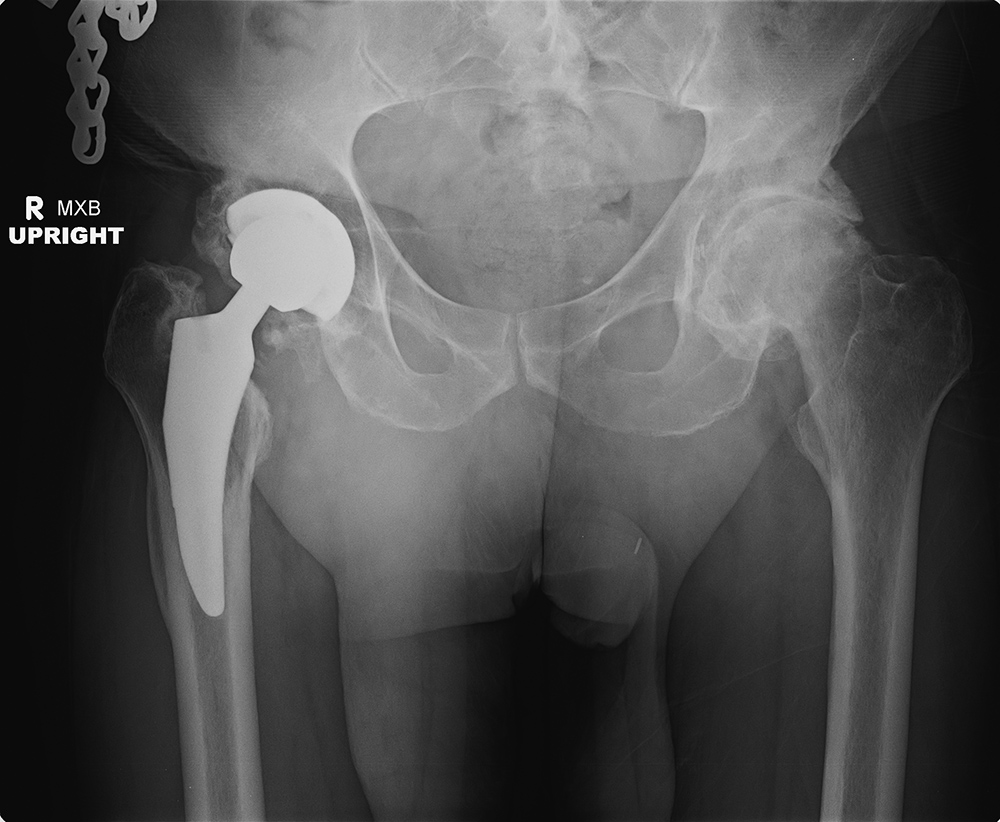

Elderly woman with bilateral press fit total hip arthroplasties. There is a dislocation on the right. |